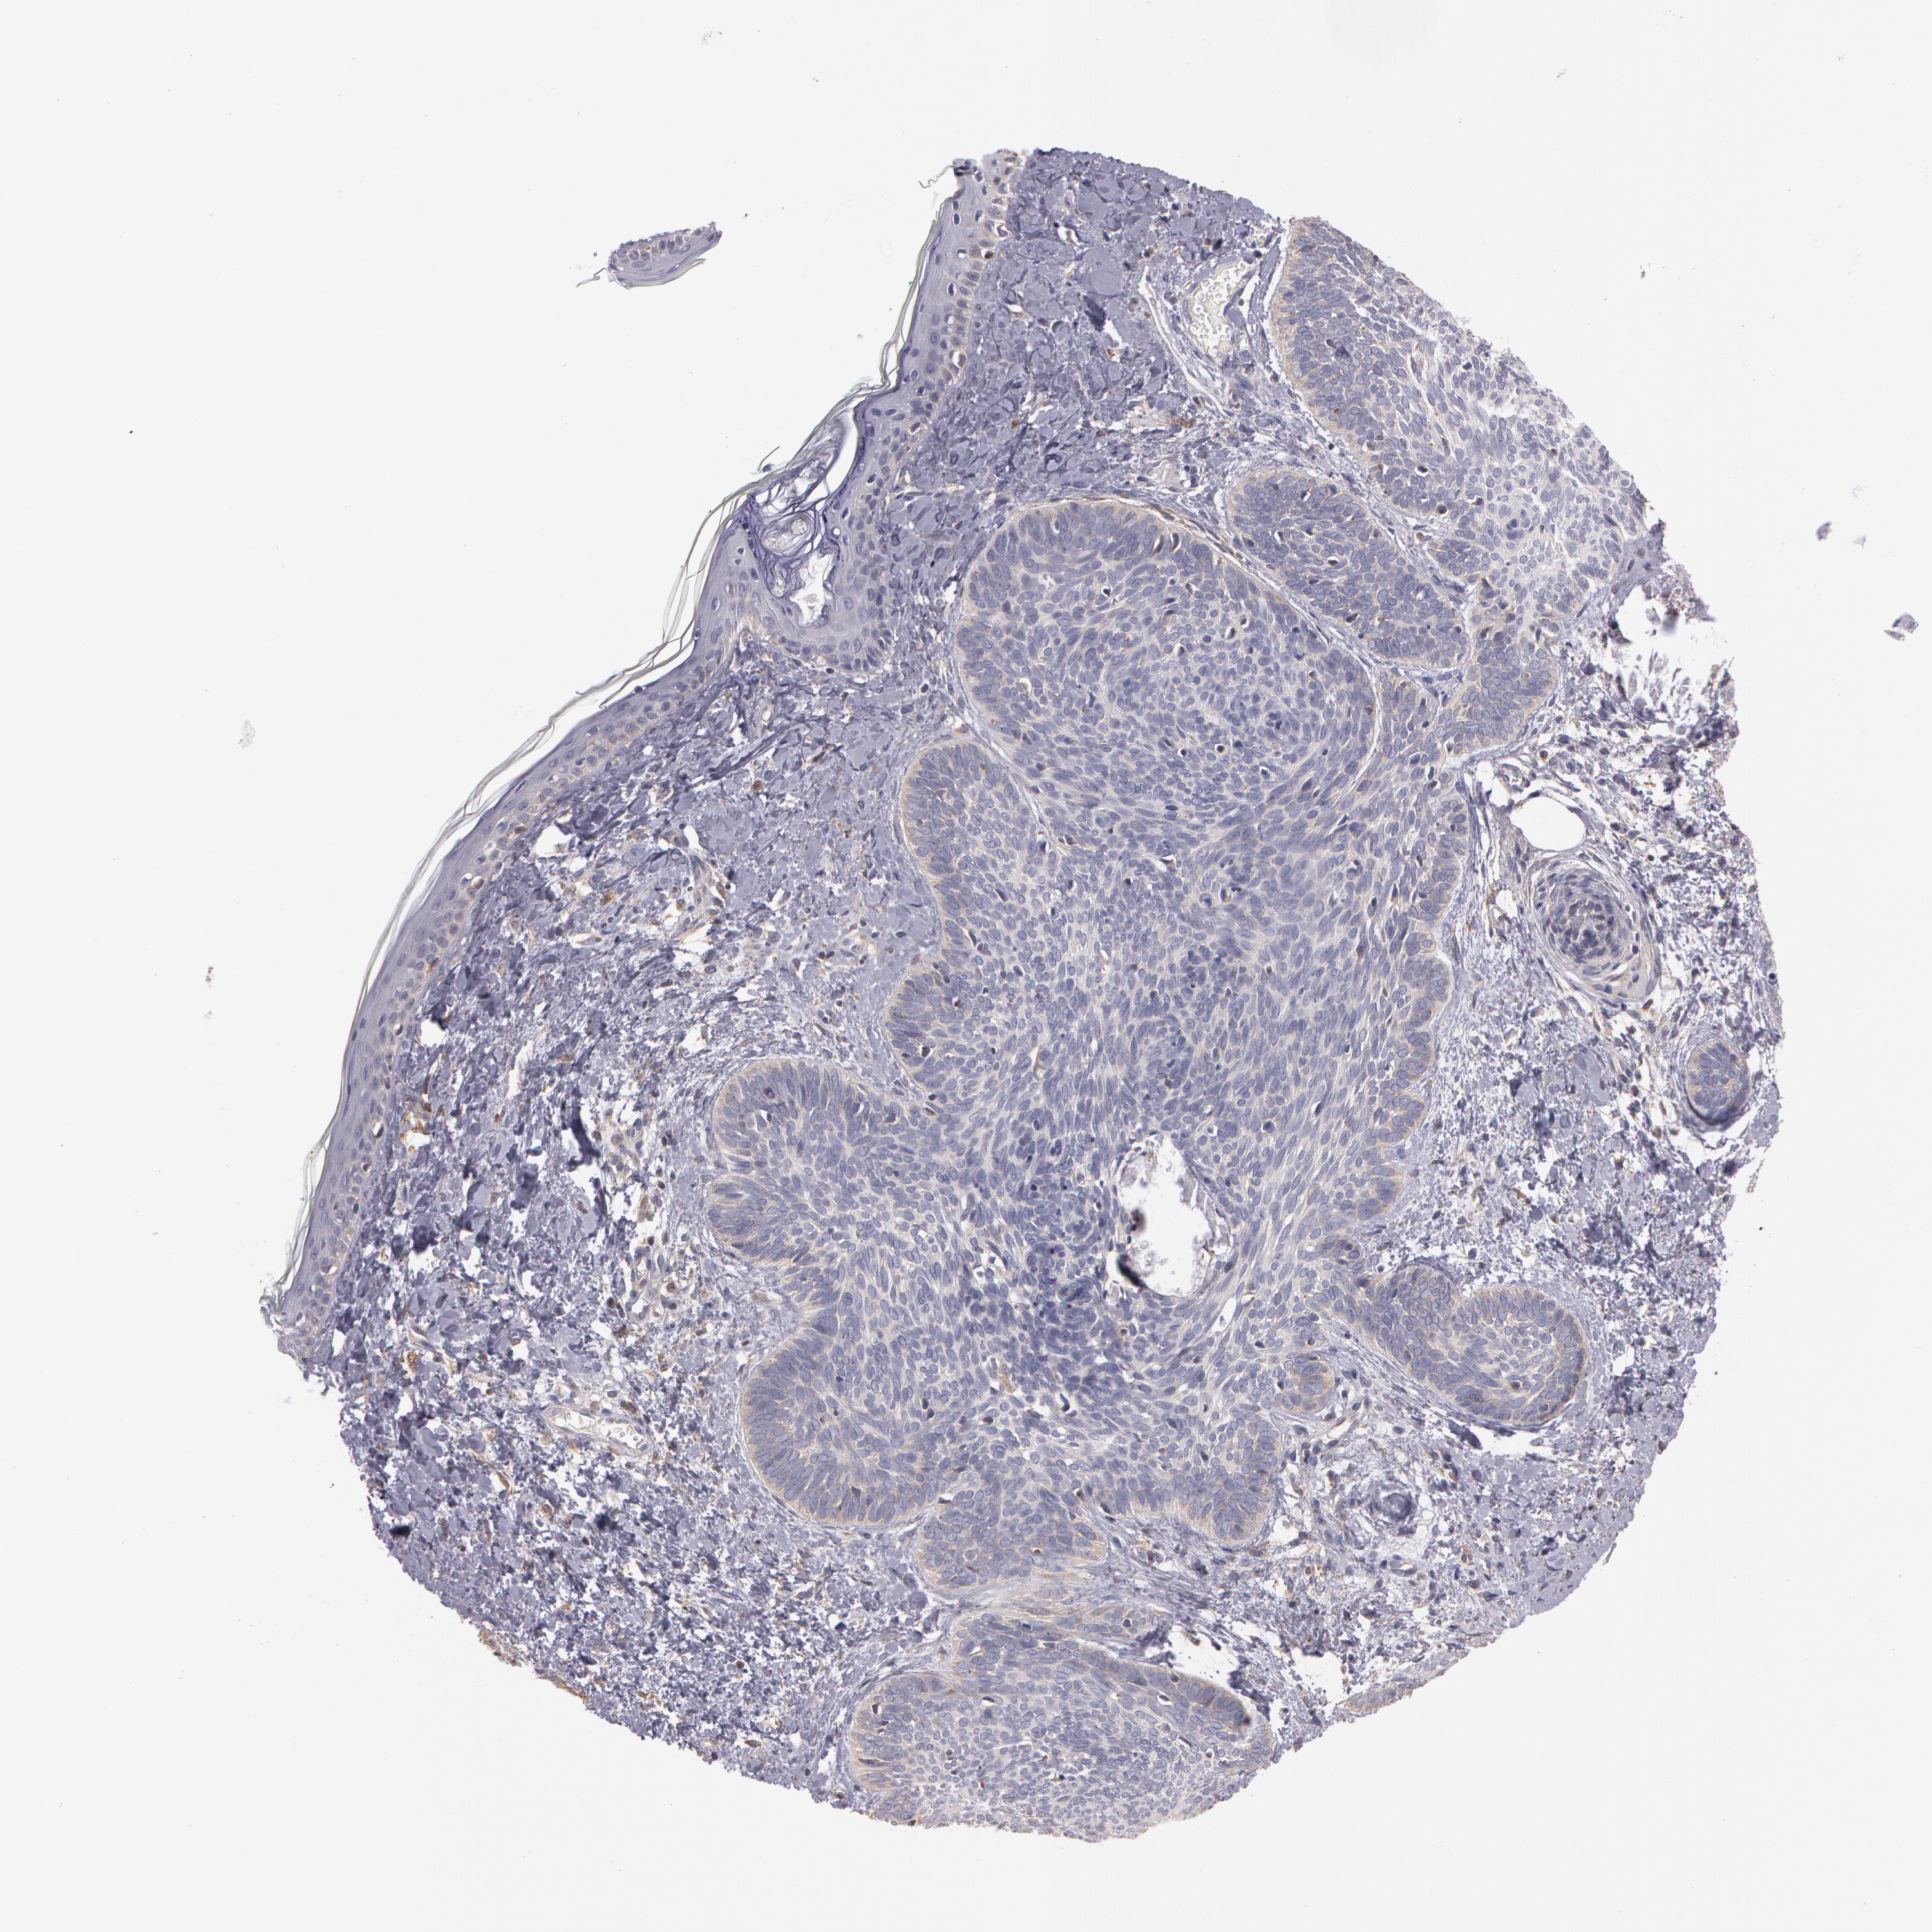

SKIN CANCER - Protein expressioni

A mouse-over function shows sample information and annotation data. Click on an image to view it in a full screen mode. Samples can be filtered based on level of antibody staining by selecting one or several of the following categories: high, medium, low and not detected. The assay and annotation is described here.

Antibody staining in the annotated cell types in the current human tissue is reported as not detected, low, medium, or high, based on conventional immunohistochemistry profiling in selected tissues. This score is based on the combination of the staining intensity and fraction of stained cells.

Each image is clickable and will lead to virtual microscopy that enables deeper exploration of all samples and also displays staining intensity scores, fraction scores and subcellular localization as well as patient and tissue information for each sample.

Antibody HPA001405

Squamous cell carcinoma, NOS

Basal cell carcinoma